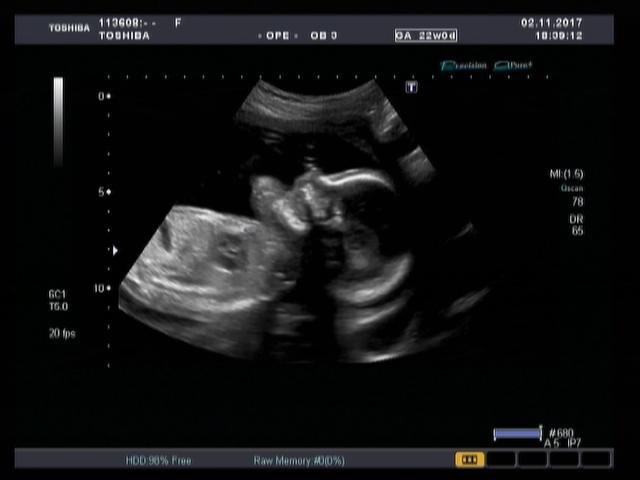

Precision Imaging (Прецизионная визуализация) ультразвуковой системы Aplio позволяют получать более реалистичные изображения и обеспечивает высокую степень послойной дифференцировки тканевых структур и анатомическую точность в визуализации деталей.

Функция автоматического измерения толщины воротникового пространства (Auto NT measurement) представляет собой инструмент для оценки размера воротниковой зоны плода, обеспечивающий превосходную воспроизводимость результатов. Эта функция позволяет проводить автоматические измерения и получать достоверные и воспроизводимые результаты при недостаточно четкой визуализации.